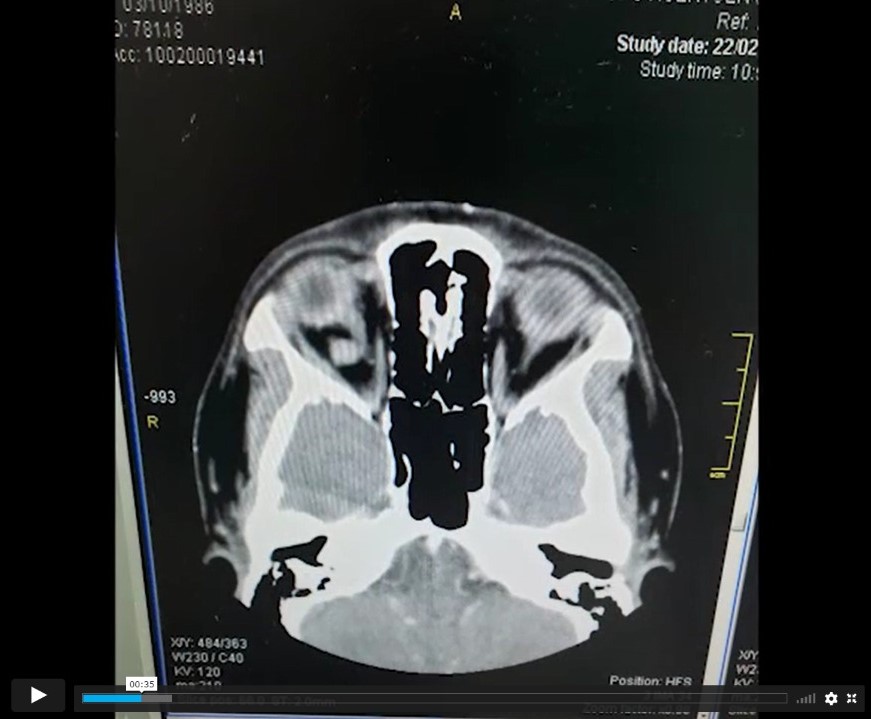

Tac se visualizan dos lesiones intraorbitarias derechas, intraconales, solidas, bien definidas, retrooculares, que contacta (la más interna) el nervio óptico y provoca una rotación externa del globo ocular.

Case Description: Pte. woman, 30 years who debuts with right proptosis, retrocular pain, diplopia, normal visual acuity. Tac two right, intracontal, solid, well-defined, retroocular intraorbital lesions are displayed that contacts (the innermost) the optic nerve and causes an external rotation of the eyeball.

Los autores presentan un video titulado “ANGIOMATOSIS CAVERNOSA INTRAORBITARIA”. La presentación es clara y con buena locución, iniciando con el cuadro clínico, una secuencia de imágenes de TAC sin y con contraste seguido de RMN que evidencian 2 cavernomas intraorbitarios. Luego da comienzo al acto operatorio en donde se notan 2 tipos de cámaras: una manual HD a mano alzada y la otra la del microscopio con menor calidad que un HD que hace que la cirugía se luzca menos. Cabe destacar la claridad en la secuencia quirúrgica de la orbitotomía lateral, la explicación de la anatomía intraorbitaria y los tips para una correcta disección y resección de los 2 hemangiomas cavernosos; por último, la reconstrucción de la pared lateral de la órbita. El video cierra con el examen de la motilidad ocular al día siguiente de la cirugía.